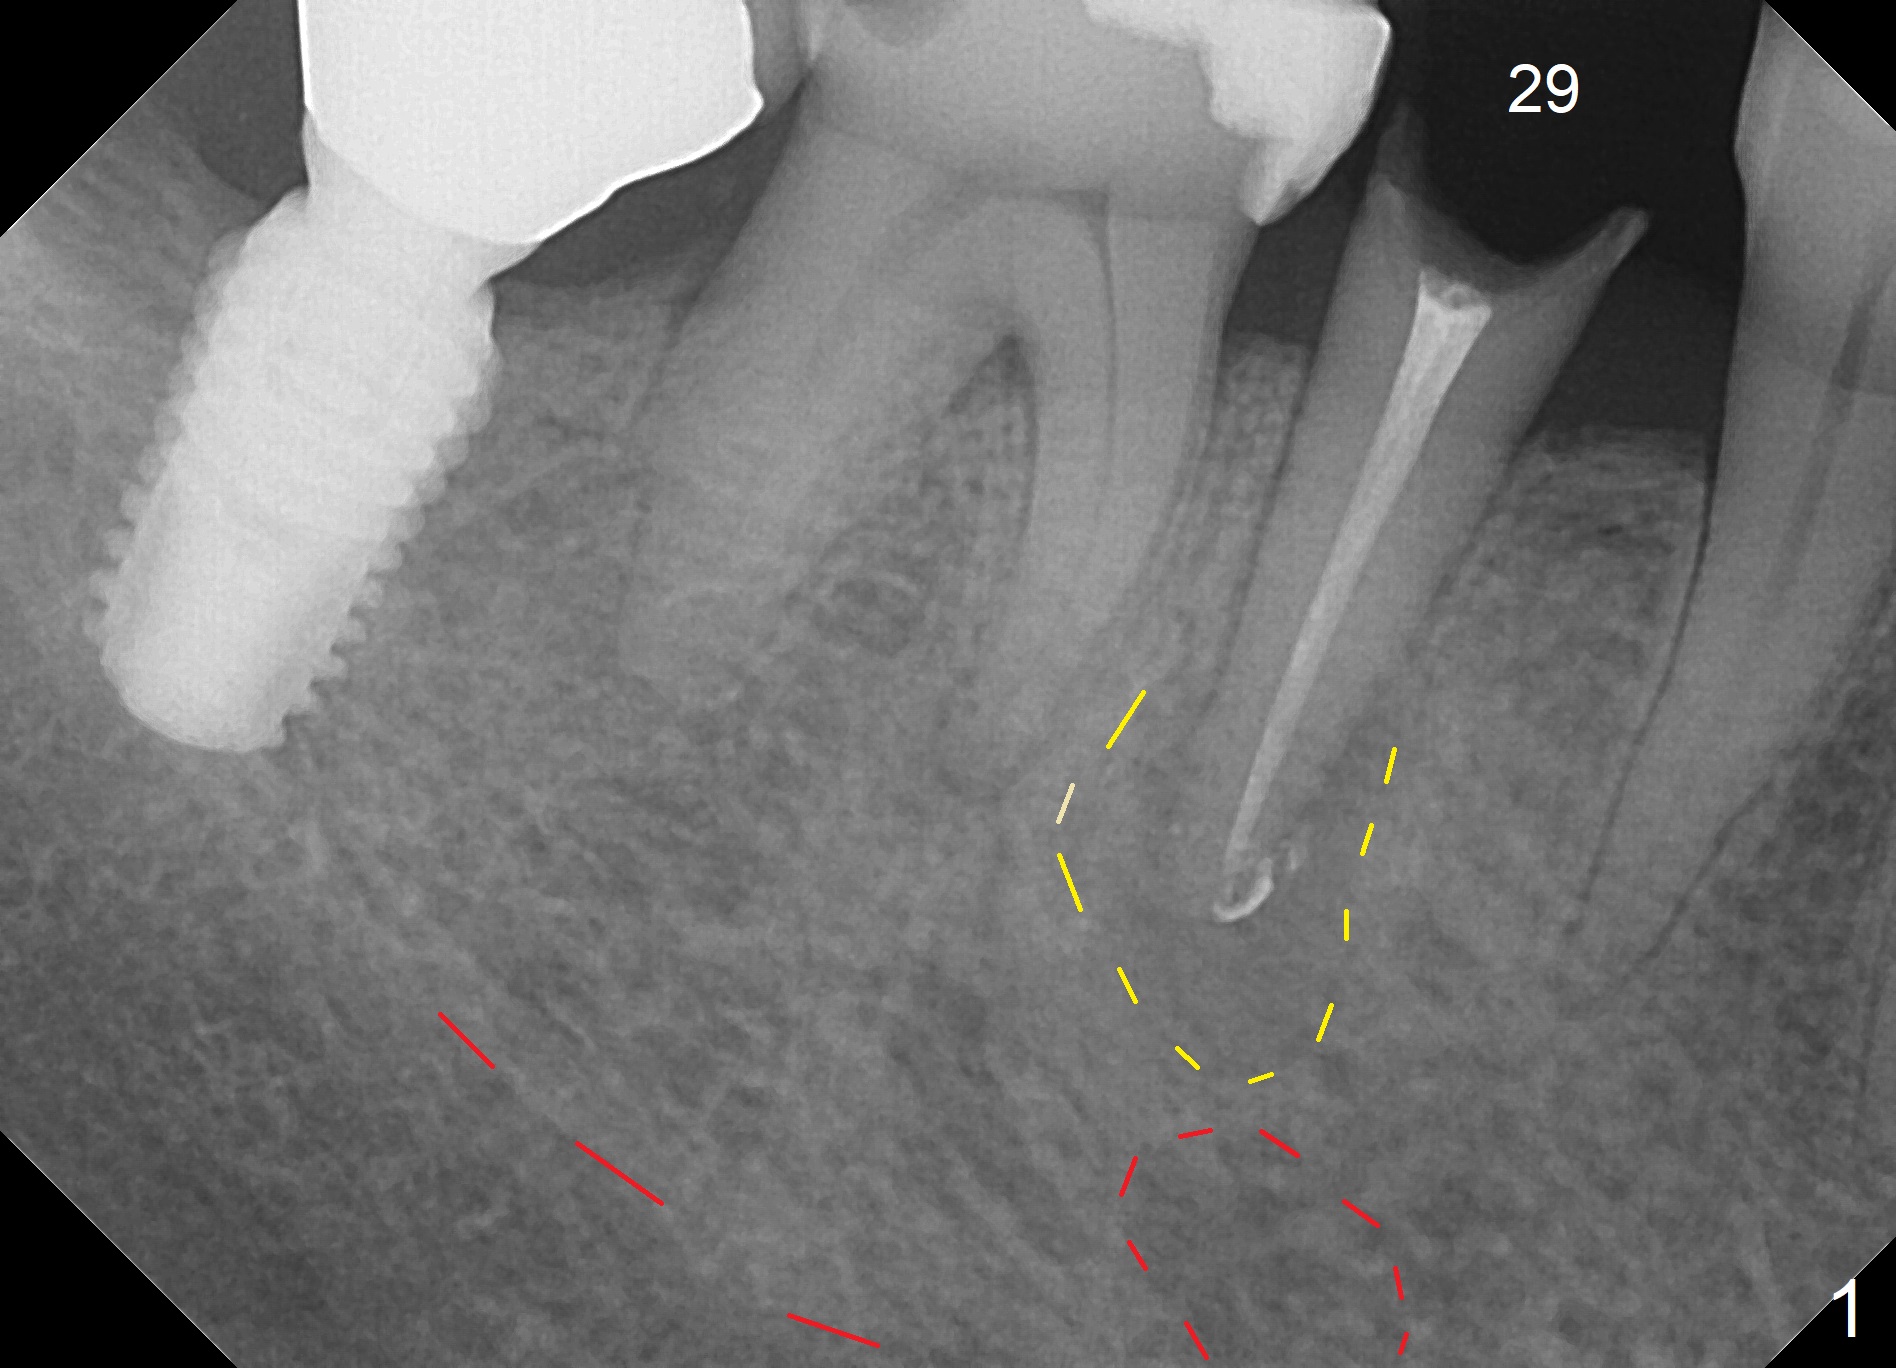

A 67-year-old woman fractures the tooth #29 three months post RCT.  There is persistent periapical radio-lucency (Fig.1 yellow dashed line), which is close to the Mental Loop (red dashed line).  Since the root of the affected tooth deviates distal, osteotomy will be established mesial (Fig.2).  To reduce the chance to injury the buccally located loop, the osteotomy should be as lingual as possible.  Initial depth will be 15 mm (shy of the Loop, bone level, 18-19 mm gingival level) with 2 mm drill, followed by the marked parallel pin.  If primary stability cannot be achieved, place a long implant as indicated in Fig.2 as long as the osteotomy remains lingual.